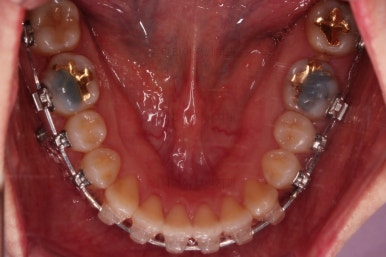

환자분이 선택하신 장치는 데이몬 클리어라고 하는 자가결찰 세라믹 장치입니다.

자가결찰 세라믹 중에 가장 심미적으로 우수한 장치가 데이몬 클리어인데요.

철사를 제외한 모든 파트가 세라믹으로 되어있습니다.

장치를 부착한 모습 참고해 주시고요.

아랫니는 중앙선을 맞추기 위해서 미니스크류를 이용해 한 쪽으로 당기는 중이고요.

이 과정에서 아랫니들이 약간은 뒤로 들어가져서 아랫입술 부위의 돌출감을 아주 약간은 줄일 수 있습니다.

윗니 임플란트 할 자리는 적절히 계속 맞춰줍니다.

중앙선도 점점 맞아지고 있어요.